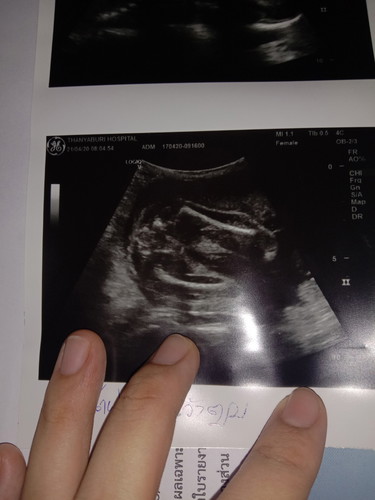

ช่วยดูให้หน่อยค่ะว่าญ.หรือช.

ญ หรือ ช ค่ะ🤗น้องนอนหันก้นให่🤗🥰 #รูปบนขวามือ🤗🥰

น่าจะหญิงนะค่ะ.ตามรูปบอกFemale

Female ผู้หญิงค่ะ